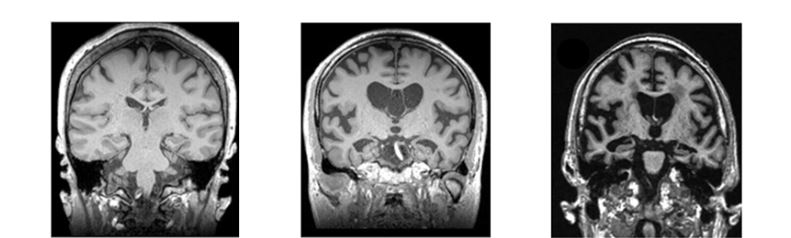

2. 뇌 MRI 검사

뇌가 어느정도 위축되어있는지 확인을 하면 치매 위험도를 알 수 있다. MRI에서 쉽게 변성의 정도, 부위를 확인할 수 있다. 따라서 MRI 검사를 하면 치매 원인 질환인 수두증, 뇌혈종, 감염 등 대사질환 또는 종양 등을 진단할 수 있다.